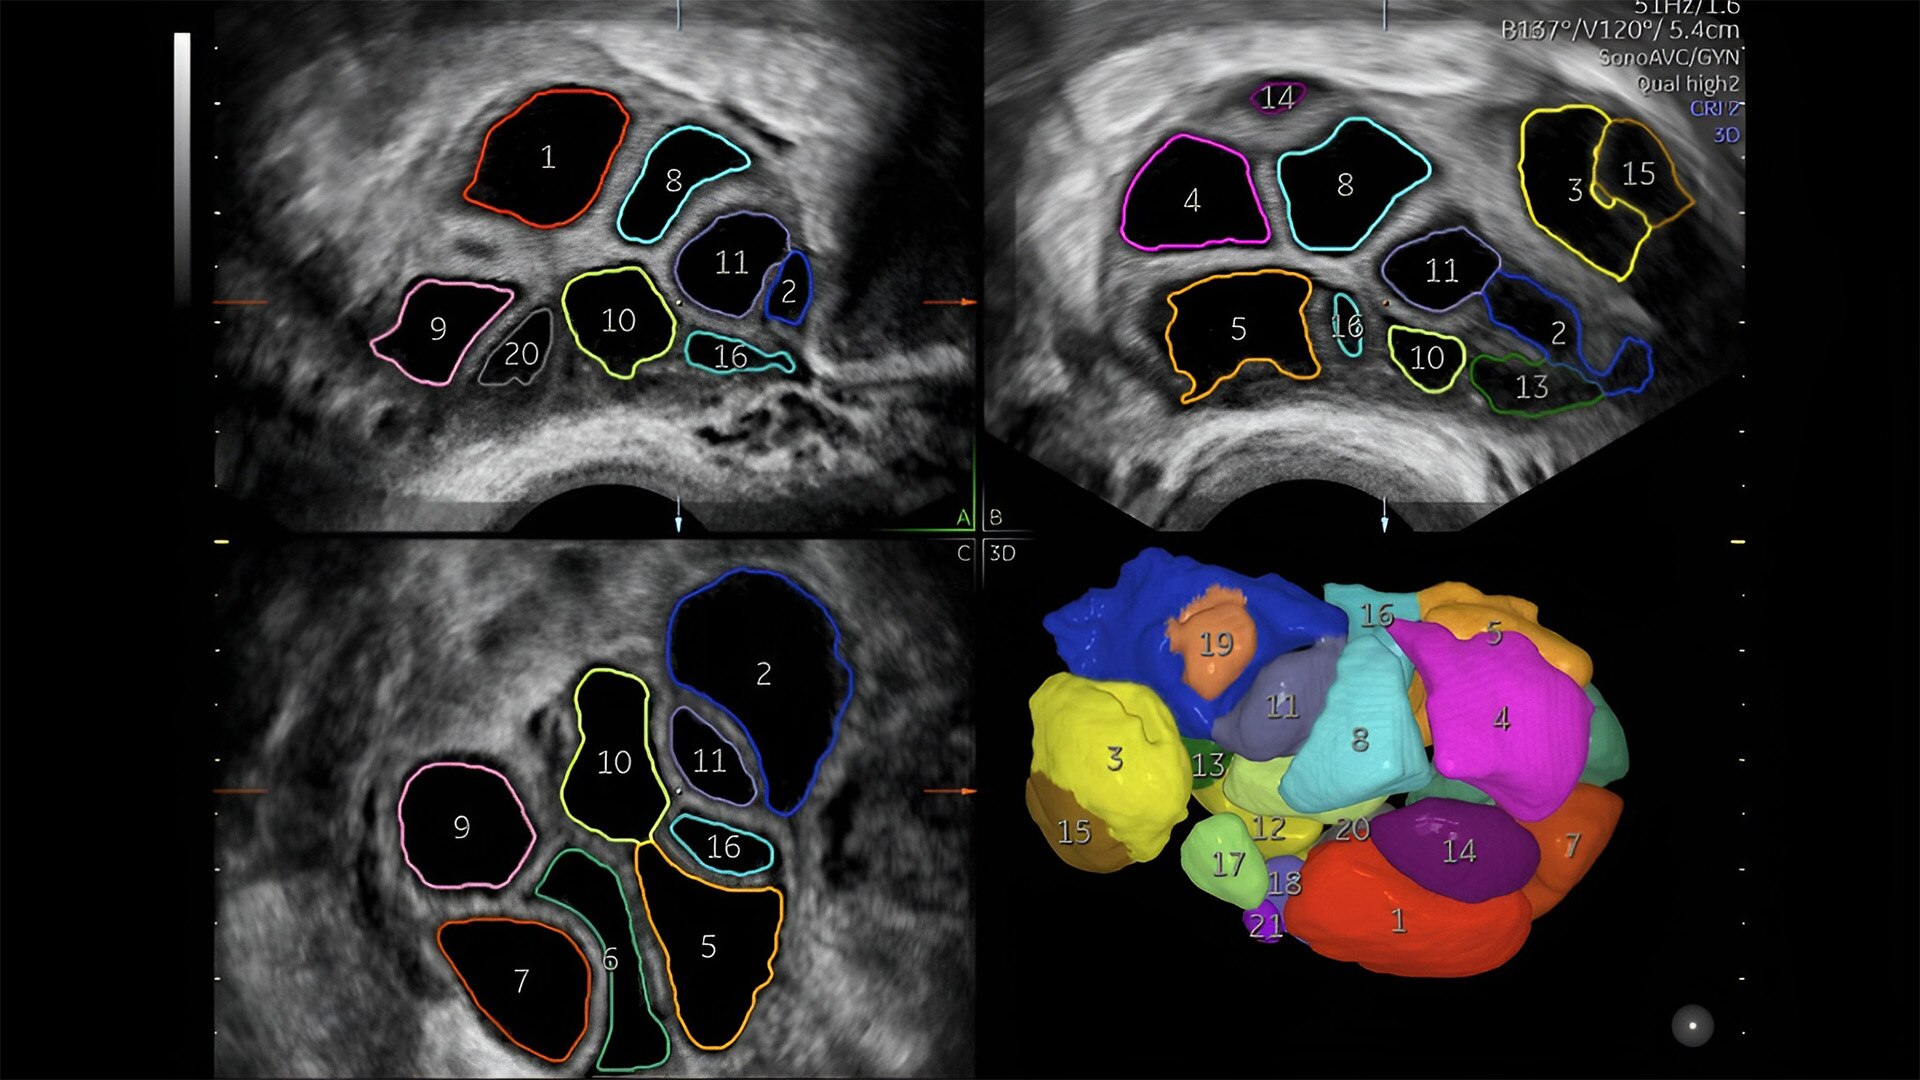

Pelvic health

Offer patient answers faster with Ai-based automation tools